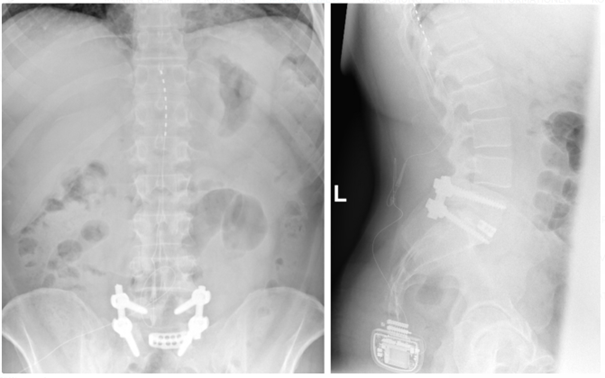

Wie bei der Rückenmarksstimulation erfolgt die Implantation eines Systems zur Dorsalganglienstimulation in zwei Schritten. Zuerst wird eine Elektrode gezielt im Bereich der Hinterwurzelganglien (Dorsalganglien) am Rücken platziert. Der Unterschied zur Rückenmarksstimulation ist hierbei die Lage der Elektrode. Im Anschluss an die Elektrodenplatzierung erfolgt eine Testphase. Bei zufriedenstellendem Ergebnis wird in einem zweiten Eingriff der Impulsgeber unter die Haut implantiert.

Durch feine elektrische Impulse wird die Weiterleitung von Schmerzsignalen zum Gehirn moduliert. Dies kann insbesondere bei Nervenschmerzen, wie dem komplexen regionalen Schmerzsyndromen (CRPS), zu einer Beschwerdelinderung führen.

Röntgenbild zur Dorsalganglienstimulation